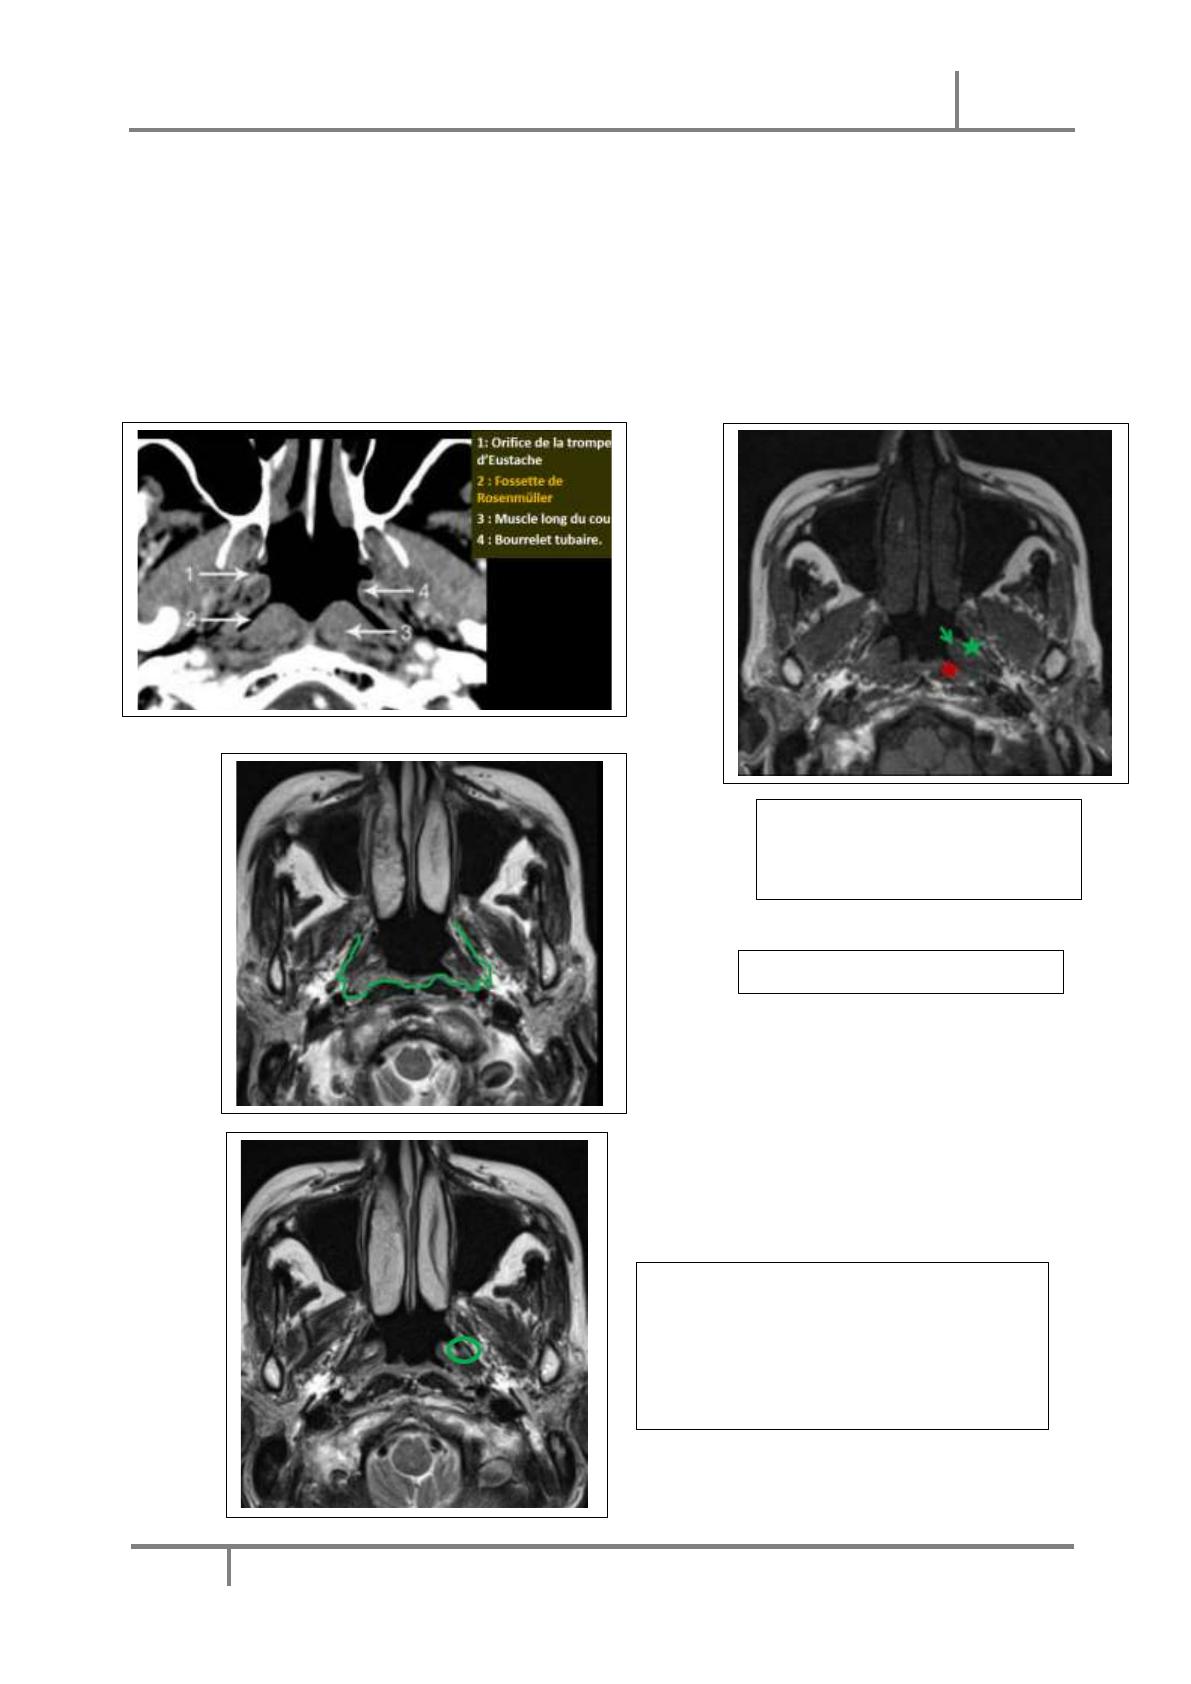

- Siège : Le point de départ est souvent la paroi latérale, dans la région de la fossette

de Rosenmüller

A. L’IRM → Examen de choix ++

- Intérêt : → « Staging des tumeurs du cavum »

o Imagerie la plus sensible pour diagnostiquer l’extension intracrânienne

o Extension aux espaces profonds de la face

o Extension péri nerveuse et péri vasculaire

- Imagerie la plus sensible pour la détection des adénopathies rétropharyngées. Technique :

o T1 sans saturation de la graisse : extension osseuse, précision anatomique des

différents espaces++ et envahissement de graisse para pharyngée

o T2 avec ou sans saturation de la graisse (selon les équipes) : pour préciser

l’extension, différencier tumeur et rétentions sinusiennes, ADPs → certaines

équipes utilisent la saturation de graisse ce qui permet de faire ressortir le

contraste entre la tumeur en hypersignal et les structures saines en hyposignal ;

d’autres préfèrent ne pas saturer la graisse pour une meilleure appréciation de

l’anatomie et des extensions intramusculaires.

o T1 Gado Fat Sat : 0.2 ml/kg de produit de contraste paramagnétique, pour préciser

l’extension

o Diffusion avec calcul de l’ADC : hypersignal B 1000 avec ↘ de l’ADC pour les

tumeurs malignes → Détection des petites tumeurs, ADPs (sensible mais non

spécifique)

o +/- complément cérébral ++ (T1, T2, Flair et Gado)